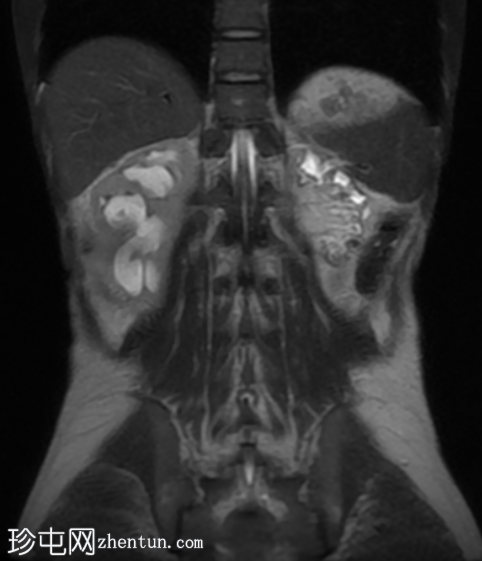

冠状位

T2加权像

5.png

再次观察到上述肾前部外生性病变,其实性成分在T1加权像上呈等高信号,在T2加权像上呈低信号,伴有碎片扩散受限和低ADC值(化脓性物质)。囊性成分内部可见液-碎片/脓液界面。可见内部低信号结石。可见肾周模糊影。该病变压迫并可能侵犯右肾盂,导致中度肾积水。

病灶不规则的低信号,以及液-液界面伴有碎屑(可能为化脓性物质)扩散受限和肾周模糊,再次高度提示炎症性病变(黄色肉芽肿性肾盂肾炎,XGP),而非可能性较小的肿瘤。

左肾萎缩,体积较小,内含多发低信号结石。